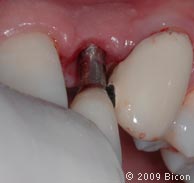

Второе посещение клиники спустя 14 недель.

25. Внешний вид после извлечения временных протезов.

26. Для раскрытия верхнего бокового правого резца сделан надрез.

27. Извлечение заглушки с помощью специального инструмента.

28. Извлечение заглушки с помощью специального инструмента.